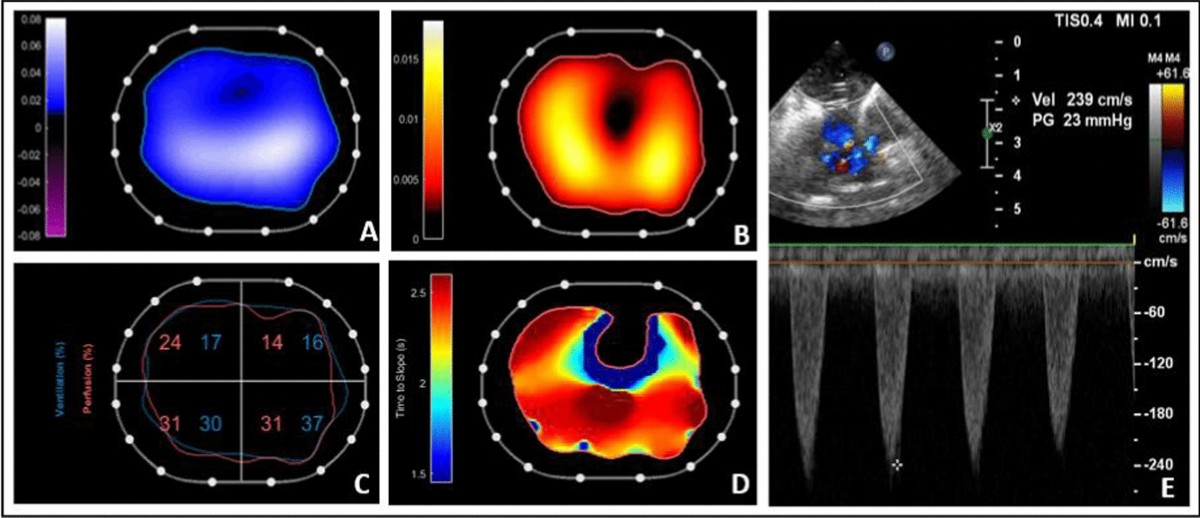

Imaging Techniques

Imaging techniques are at the forefront of measuring lung perfusion. Technologies like CT scans and MRI offer a non-invasive window into the body. These methods provide high-resolution images, allowing doctors to pinpoint areas where blood flow might be compromised.

Another popular imaging method is the use of nuclear medicine scans, such as a V/Q scan. This involves inhaling a radioactive gas and injecting a radioactive substance into the bloodstream. The resulting images reveal how well air and blood are distributed throughout the lungs.